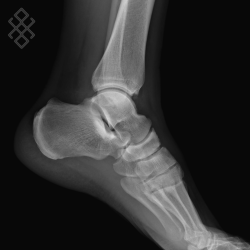

Radiographie de la Cheville